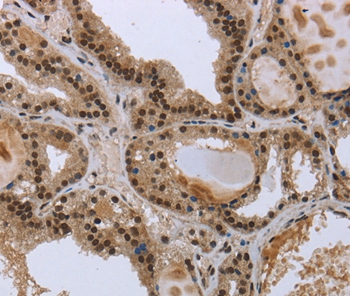

Immunohistochemical analysis of paraffin-embedded Human colon cancer tissue using #36500 at dilution 1/50.